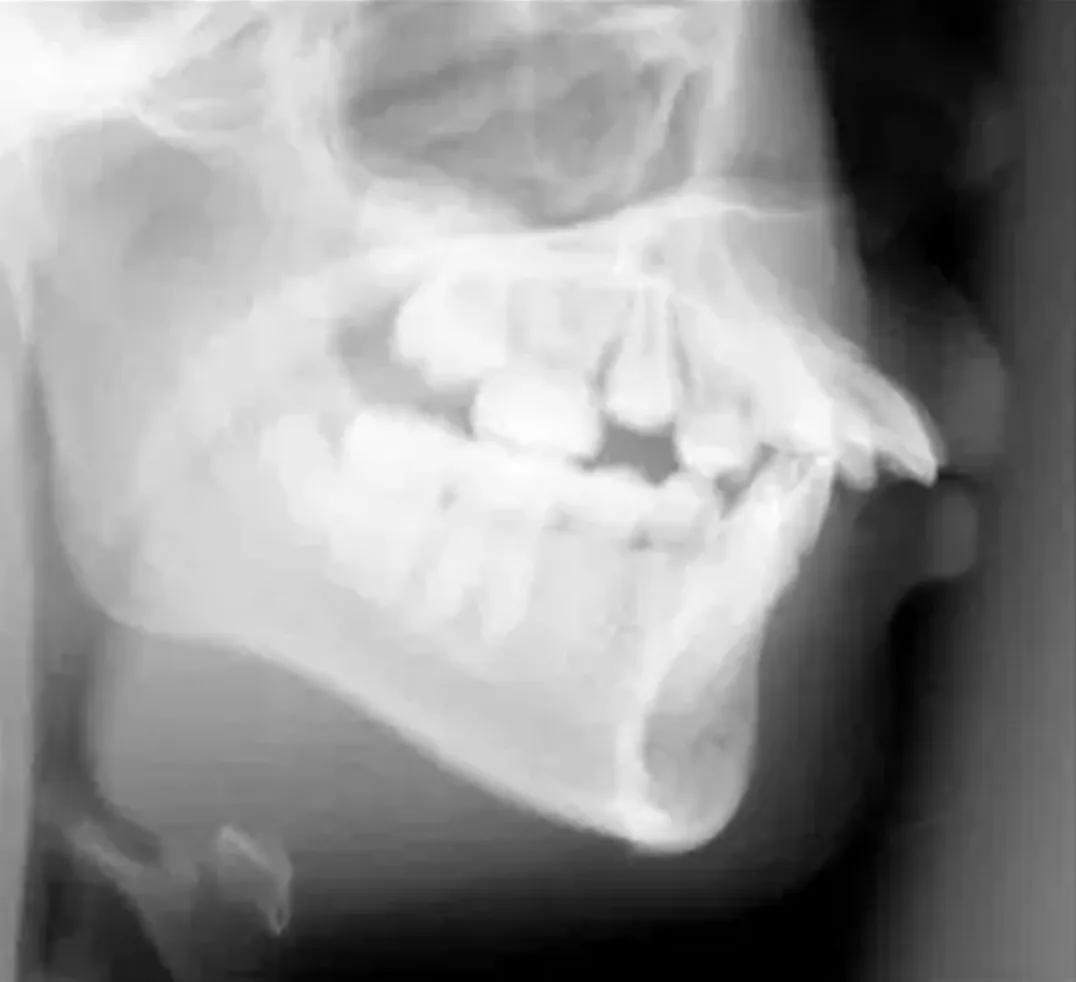

デコボコの歯並びや出っ歯などの原因のひとつとして、永久歯の1本1本が大きすぎることが挙げられます。例えば、あなたご自身の上顎の歯が平均的な大きさに比べて、1本につき1mmずつ大きかった場合は、上顎14本×1mmで合計14mm、おおよそ2本分の歯の並ぶスペースが足りないことになります。土台となる顎骨に十分なスペースが確保できない場合、歯がうまく並びきることができず、デコボコの歯並びや出っ歯の状態になってしまいます。

歯を並べるスペースを確保するため、歯を抜かずに矯正装置をつけて顎を拡大すれば、実際のところ歯を並べることだけは可能です。しかし患者さんによっては、さらに口元が突き出てしまい、口が閉じにくくなったりする場合もあります。また、無理な拡大は治療後のかみ合わせの安定性にも関わってきます。